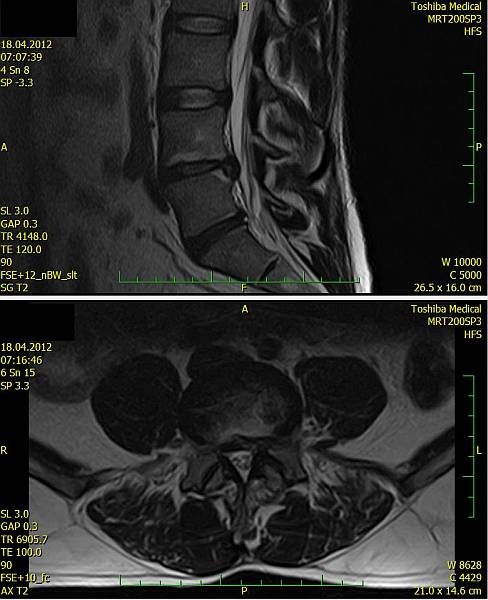

2. Muž, 41 let. Na MR objemná hernie L4/5 velikosti 11mm téměř vyplňující páteřní kanál, útlak nervových kořenů. Opakovaně doporučována operace, kterou pacient odmítl. Jako alternativu zvolil ozonoterapii s aplikací ozonu do disku L4/5 a periradikulárně. Byly aplikovány celkem 3 dávky ozonu. Viz obr.7a

Na kontrolním MR po 6 měsících je patrná výrazná redukce velikosti hernie, vymizely fragmenty, uvolnil se páteřní kanál a do značné míry i nervové kořeny. Subjektivně výrazná úleva téměř k normálu. Viz obr. 7b